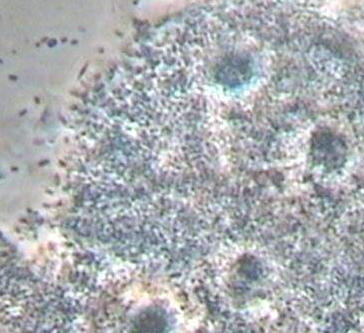

线索细胞是加德纳杆菌或小杆菌感染正常的鳞状上皮细胞,使正常的鳞状上皮细胞形状发生改变,如边缘不齐整、不光滑、清晰度不高等。其为阴道脱落鳞状上皮细胞上黏附大量加特纳杆菌等厌氧菌的一种形状表现。当女性分泌物中出现大量线索细胞时,一般预示患了细菌性阴道病。当然也要结合别的几项至关重要指标值来确诊,一般是pH值、胺试验及分泌物增多性状等指标值。

全自动白带香蕉视频免费APP厂家发现线索细胞是细菌性阴道病的最比较敏感、最特异性的体征,可根据胺试验阳型及有线索细胞即可做出细菌性阴道病的诊断。